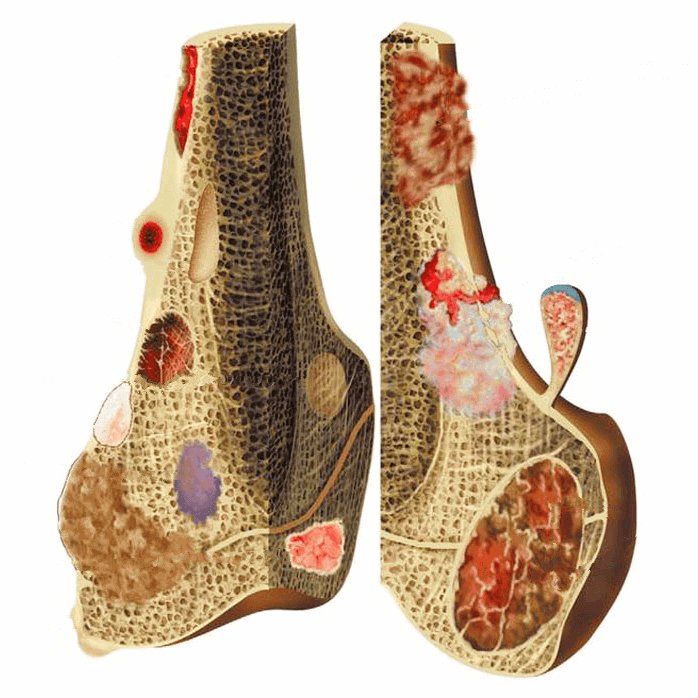

– Khớp gối bao gồm phần dưới của xương đùi và phần trên của xương chày (được gọi là mâm chày), đầu trên xương mác và xương bánh chè. Đầu xương được bọc bởi lớp sụn khớp. Một lớp sụn đệm vào giữa chúng gọi là sụn chêm trong (hình chữ C) và một lớp sụn bên ngoài gọi là sụn chêm ngoài (hình chữ O).

– Hai đầu xương được giữ lại với nhau bằng các dây chằng, ở hai bên là dây chằng trong và dây chằng ngoài, ở trung tâm khớp là dây chằng chéo trước và dây chằng chéo sau. Xương bánh chè là một xương vừng, nó nằm ở dưới gân cơ tứ đầu đùi và có vai trò bảo vệ gân tứ đầu cũng như tăng cánh tay đòn của gân này.

– Ngoài ra còn có bao hoạt dịch nằm ở mặt trong gối có cấu tạo là các sợi xơ mềm và mỡ, nó có thể tiết dịch hoạt dịch để làm trơn và nuôi dưỡng sụn khớp, nó cũng có vai trò chống lại nhiễm khuẩn viêm.